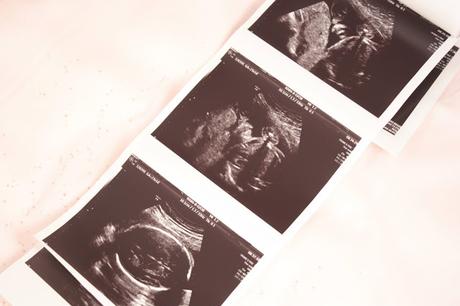

Nous attendions avec impatience ce moment car c'est durant les échographies que nous pouvons vraiment être rassurés que tout se passe bien pour Bébé et parce que comme tout futurs parents (je suppose) voir son bébé en image est un moment très privilégié et tellement magique.

L'échographe regarde comment est positionnée Notre Princesse, elle a bien la tête en bas comme nous l'avait dit la sage-femme le mois précédent. Ensuite il regarde son crâne, ses contours, son cerveau. Il nous montre son visage. On la voit bien, qu'est-ce qu'elle a grandi! Nous ne souhaitions pas d'échographie en 3D si cela n'était pas nécessaire et n'en avons pas eu besoin pour déjà apercevoir les traits de son visage. A ce moment je suis aux Anges! Mais pas pendant longtemps... J'ai été déçu, très déçu de n'avoir vu le visage de ma fille qu'une seconde, voir deux peut-être. L'échographe ne s'est pas du tout attardé, dommage.

Il est passé très vite aux autres parties de son corps: colonne vertébrale, organes internes (estomac, reins, foie, cœur...).

Il continue donc l'examen, nous montre ses jambes, ses bras, ses mains... Et termine. L'échographe a visiblement pu tout voir, je peux me rhabiller.

Même sur les photos de mon échographie, il n'y en a que trois où l'on voit son visage... Le reste est assez flou pour moi. Je sais qu'elle a grandi qu'on ne peut plus désormais la voir en entière sur écran, mais je ne m'attendais pas à ne presque rien percevoir...